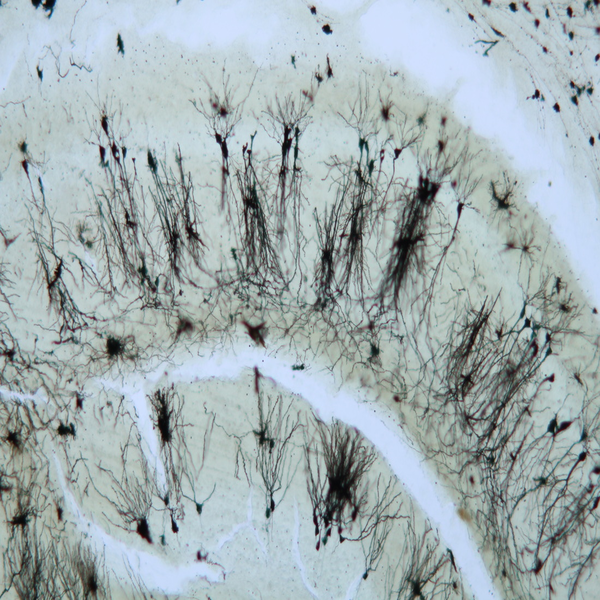

- General and specialized tissue and cell staining

- Prepare educational slides for students from all available tissues

Histological methods includes sample processing in the pathology laboratory, preparation of the slide and its examination under a microscope, sample fixation, molding, microtome cutting, staining and assembly of the slides.

On the other hand, in cutting-edge sciences such as tissue engineering, the use of up-to-date techniques for section preparation and cell tracking and engineered tissue structure has contributed significantly to the development of new studies.